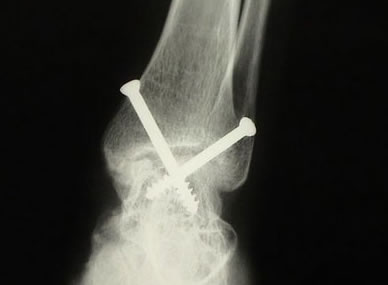

Durante a artroscopia para artrose, verificamos e tratamos várias lesões. Realizamos sinovectomia, desbridamento e retirada de corpos livres, conforme citado anteriormente. A abrasão do osso subcondral exposto e o restabelecimento dos canais de vascularização e formação de fibrocartilagem podem trazer benefícios. O desbridamento artroscópico na artrose de tornozelo é um procedimento paliativo, que visa alívio temporário da dor em pacientes que ainda apresentam alguma amplitude de movimento. Sendo assim, se houver indicação para artrodese via artroscópica, removemos toda a superfície articular do pilão tibial, domo talar e superfícies talomaleolares medial e lateral (cruentizadas) com shaver e curetas até a exposição de osso esponjoso viável. Tomamos os devidos cuidados para evitar retirada excessiva de cartilagem e osso subcondral, que podem criar deformidades em varo ou valgo. Deformidades angulares prévias podem ser corrigidas artroscopicamente ou via aberta.

Ressecamos o osteófito anterior para possibilitar a redução do domo talar na articulação do tornozelo. Após preparar a área a ser artrodesada, inserimos dois guias canulados para o drill, um lateralmente através do maléolo lateral e um medialmente, através do maléolo medial. Porém, a angulação dos guias canulados será de 30° inferior e 30° anterior, partindo dos maléolos. Utilizamos fluoroscopia para verificar a posição correta da artrodese. No plano sagital, desejamos a posição neutra de dorsiflexão e flexão plantar do tornozelo e no plano coronal o calcâneo deve estar em 5° de valgo. Finalmente, utilizando parafusos canulados de 6,5mm através do guia, concluímos a artrodese.